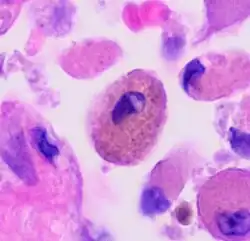

| A "smoker's macrophage", with yellow to light brown and finely granular cytoplasmic pigment. | |

Respiratory bronchiolitis is a lung disease associated with tobacco smoking.[1] In pathology, it is defined by the presence of "smoker's macrophages".[1] When manifesting significant clinical symptoms it is referred to as respiratory bronchiolitis interstitial lung disease (RB-ILD).[1]

- Pathologic: Lung biopsy with "smoker's macrophages" limited to distal airspaces and peribronchiolar airspaces, and minimal to absent peribronchiolar interstitial fibrotic thickening